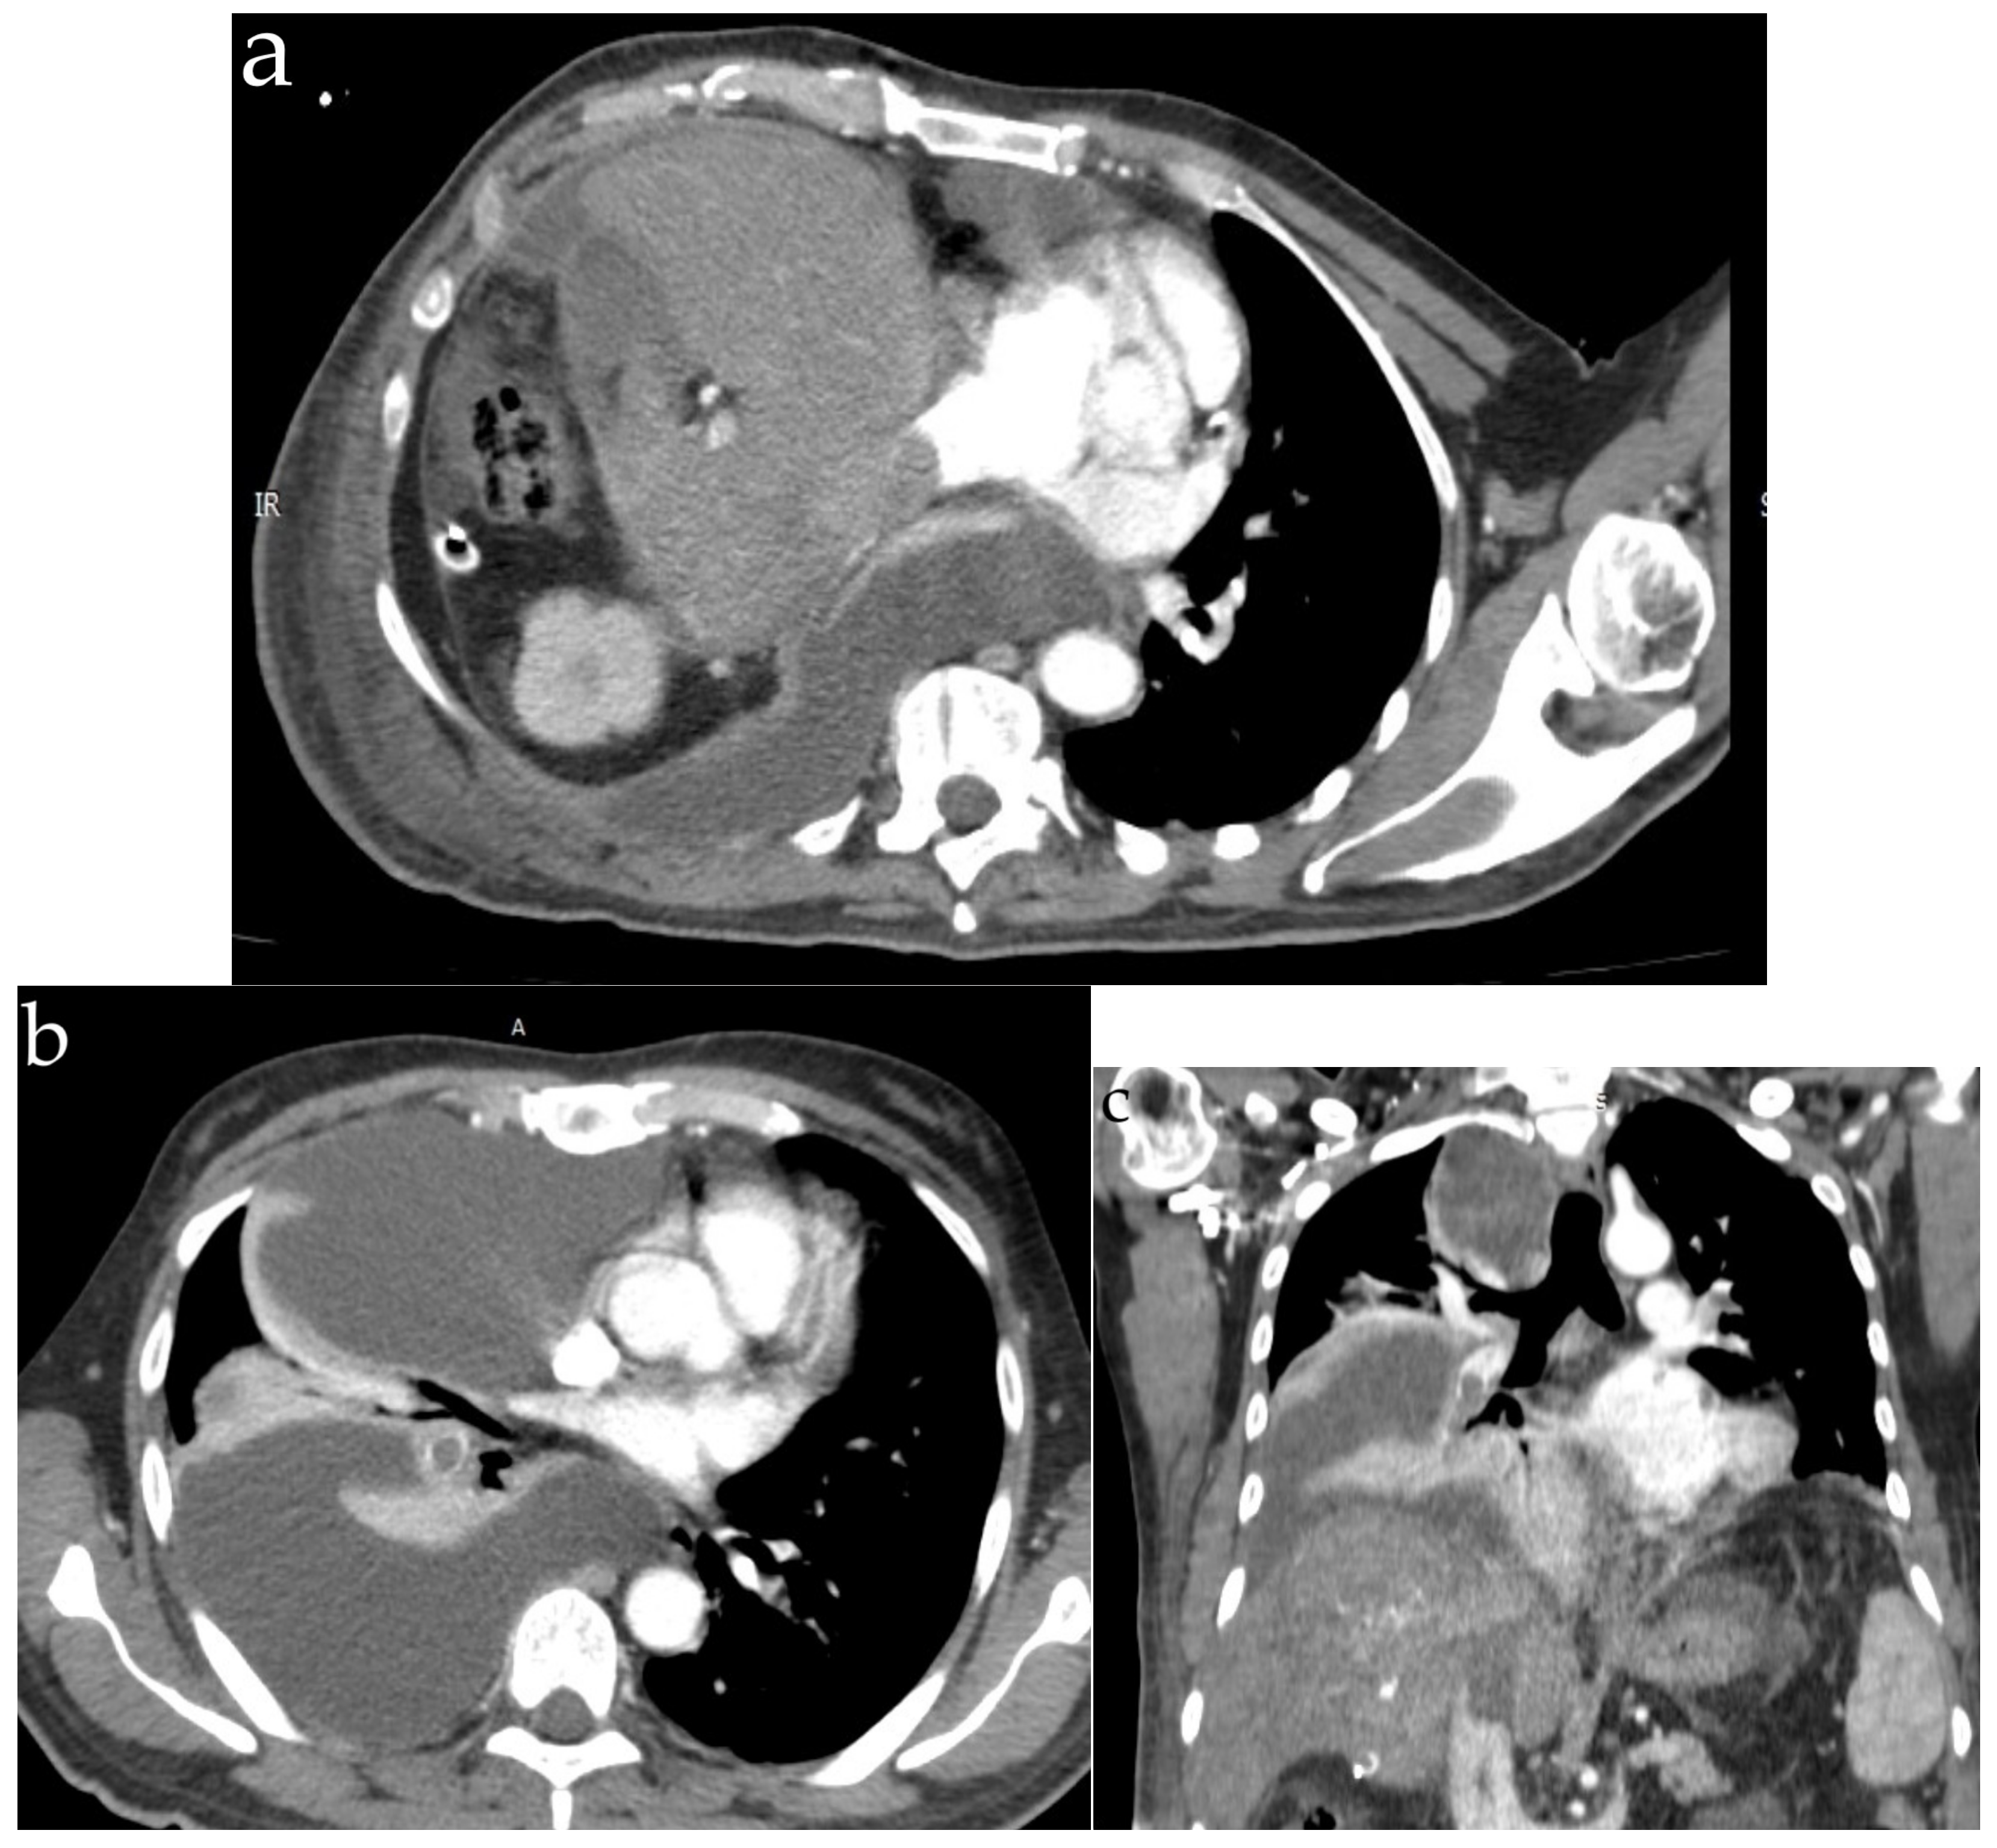

5. Septic Embolism

5.2. Diagnosis

| Computer tomography | Small amount of air in the main pulmonary artery, on the right heart or systemic veins; in severe cases, pulmonary hypertension and right heart strain are found | Ground-glass opacities, interlobar septal thickening with the pattern of “crazy paving” | Diffuse bilateral ground-glass opacities | Bilateral lung nodules, located mainly in the peripheral lung areas and in the lower lobes, mediastinal or hilar lymphadenopathy, a dilated pulmonary branch (mycotic aneurysm) and feeding vessel sign | The classic finding (affected centrilobular arteries) is an image of “tree-in-bud”; in cases where the main arteries are affected, the findings are filling defects that resemble acute or chronic pulmonary emboli |